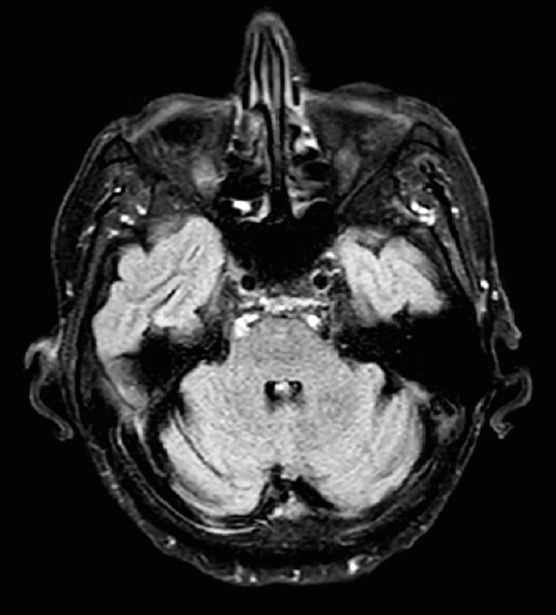

a) In T2WI magnetic resonance image, we can see hyperintensity at the splenium of the corpus callosum in sagittal sequences. b) In T2-FLAIR we also observed hyperintensity at the splenium of the corpus callosum in axial sequences sequences. c) In axial DWI sequences, we appreciated hyperintensities in bilateral middle cerebellar peduncles, also known as MCP-sign. d) In T2-FLAIR we also observed the MCP-sign.

A follow-up brain magnetic resonance image showed the resolution of the hyperintensity in middle cerebellar peduncles (in T2-FLAIR sequences).